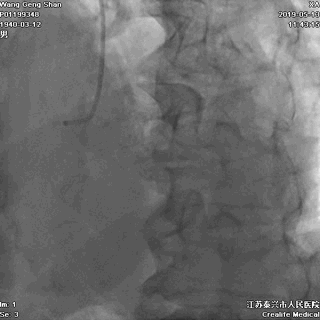

一、冠脉造影基线资料

回旋支开口狭窄90%,

中间支开口狭窄90%,

左主干尾部狭窄50%并延展至前降支近段,

前降支近段病变伴中段局限性狭窄